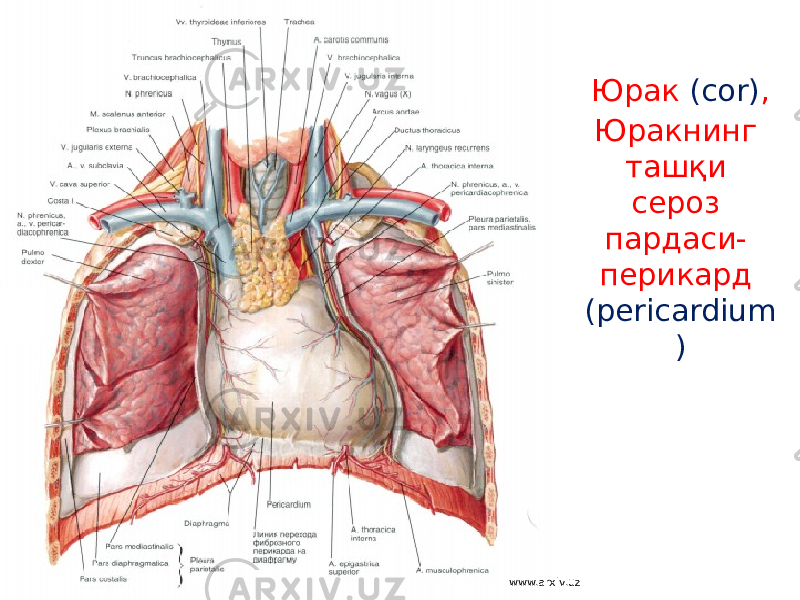

Анатомия Сердца: Расположение и Функции